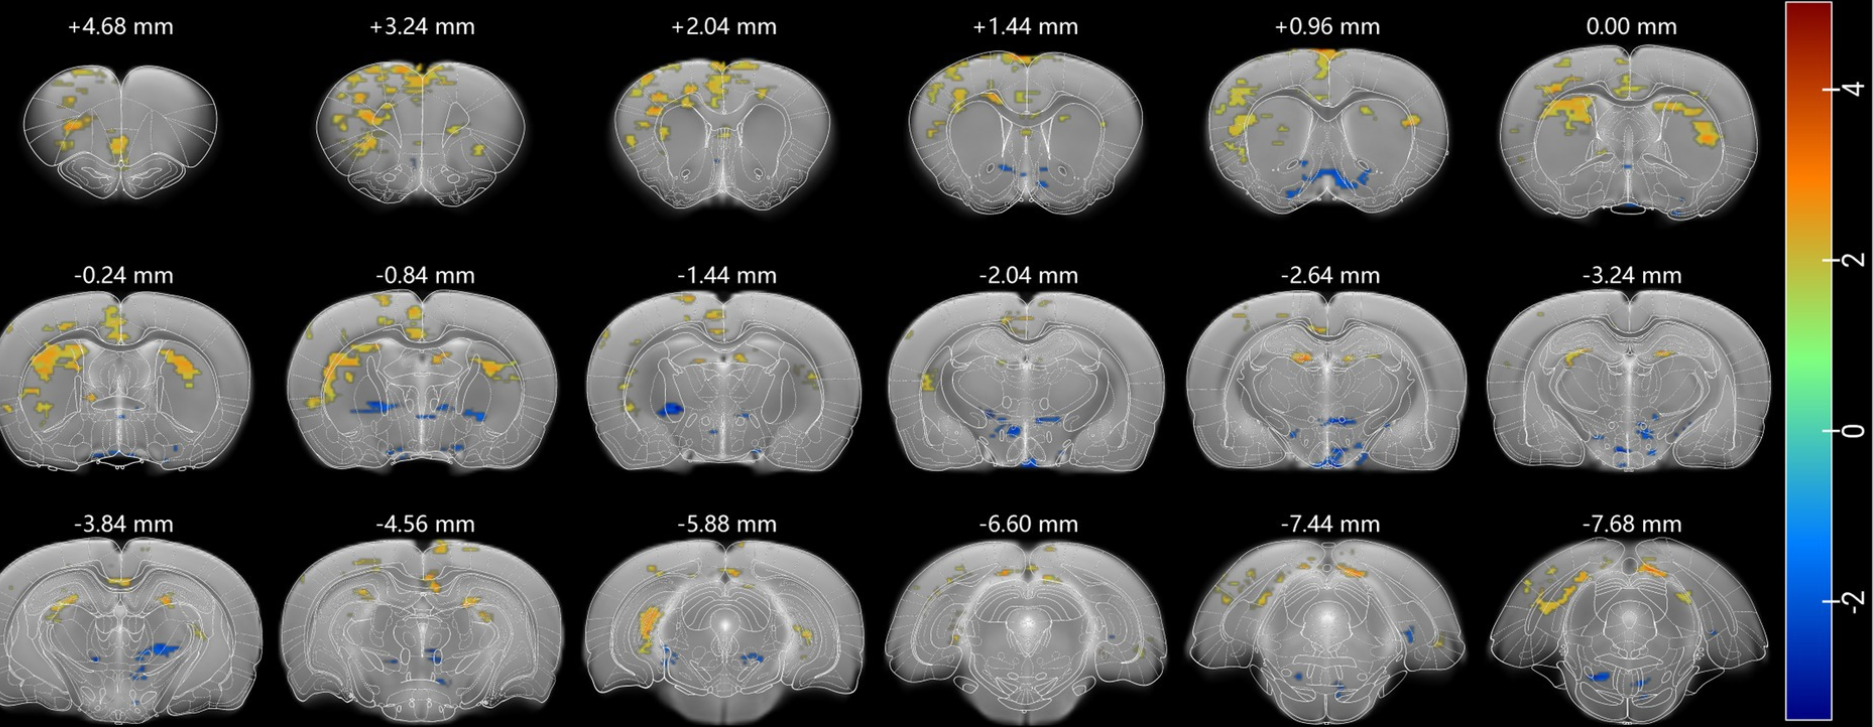

Thanks for this Atlas. I was wondering, if there is a file where

the atlas just shows segmentation as outlines? I want a similar

result as in this picture (attached).